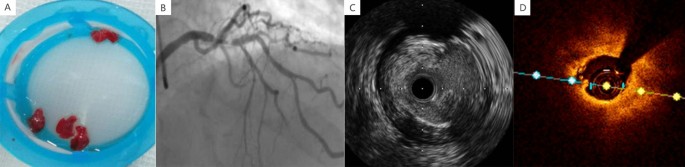

As a non-peptide GPIIb/IIIa antagonist, tirofiban can prevent the binding of fibrinogen to platelet GPIIb/IIIa receptors in order to stop the platelet aggregation and ACS development, thus effectively reducing the risks of thrombosis formation and shedding, distal embolism, no-reflow, and sudden death. Therefore, tirofiban has been recommended by relevant guidelines as a powerful anti-platelet drug that acts on the ultimate anti-platelet pathway if the thrombotic complications occur5. The images of in vitro thrombosis, angiography, and intracavity in patients with high thrombotic load were presented from A to D in Fig. 1.